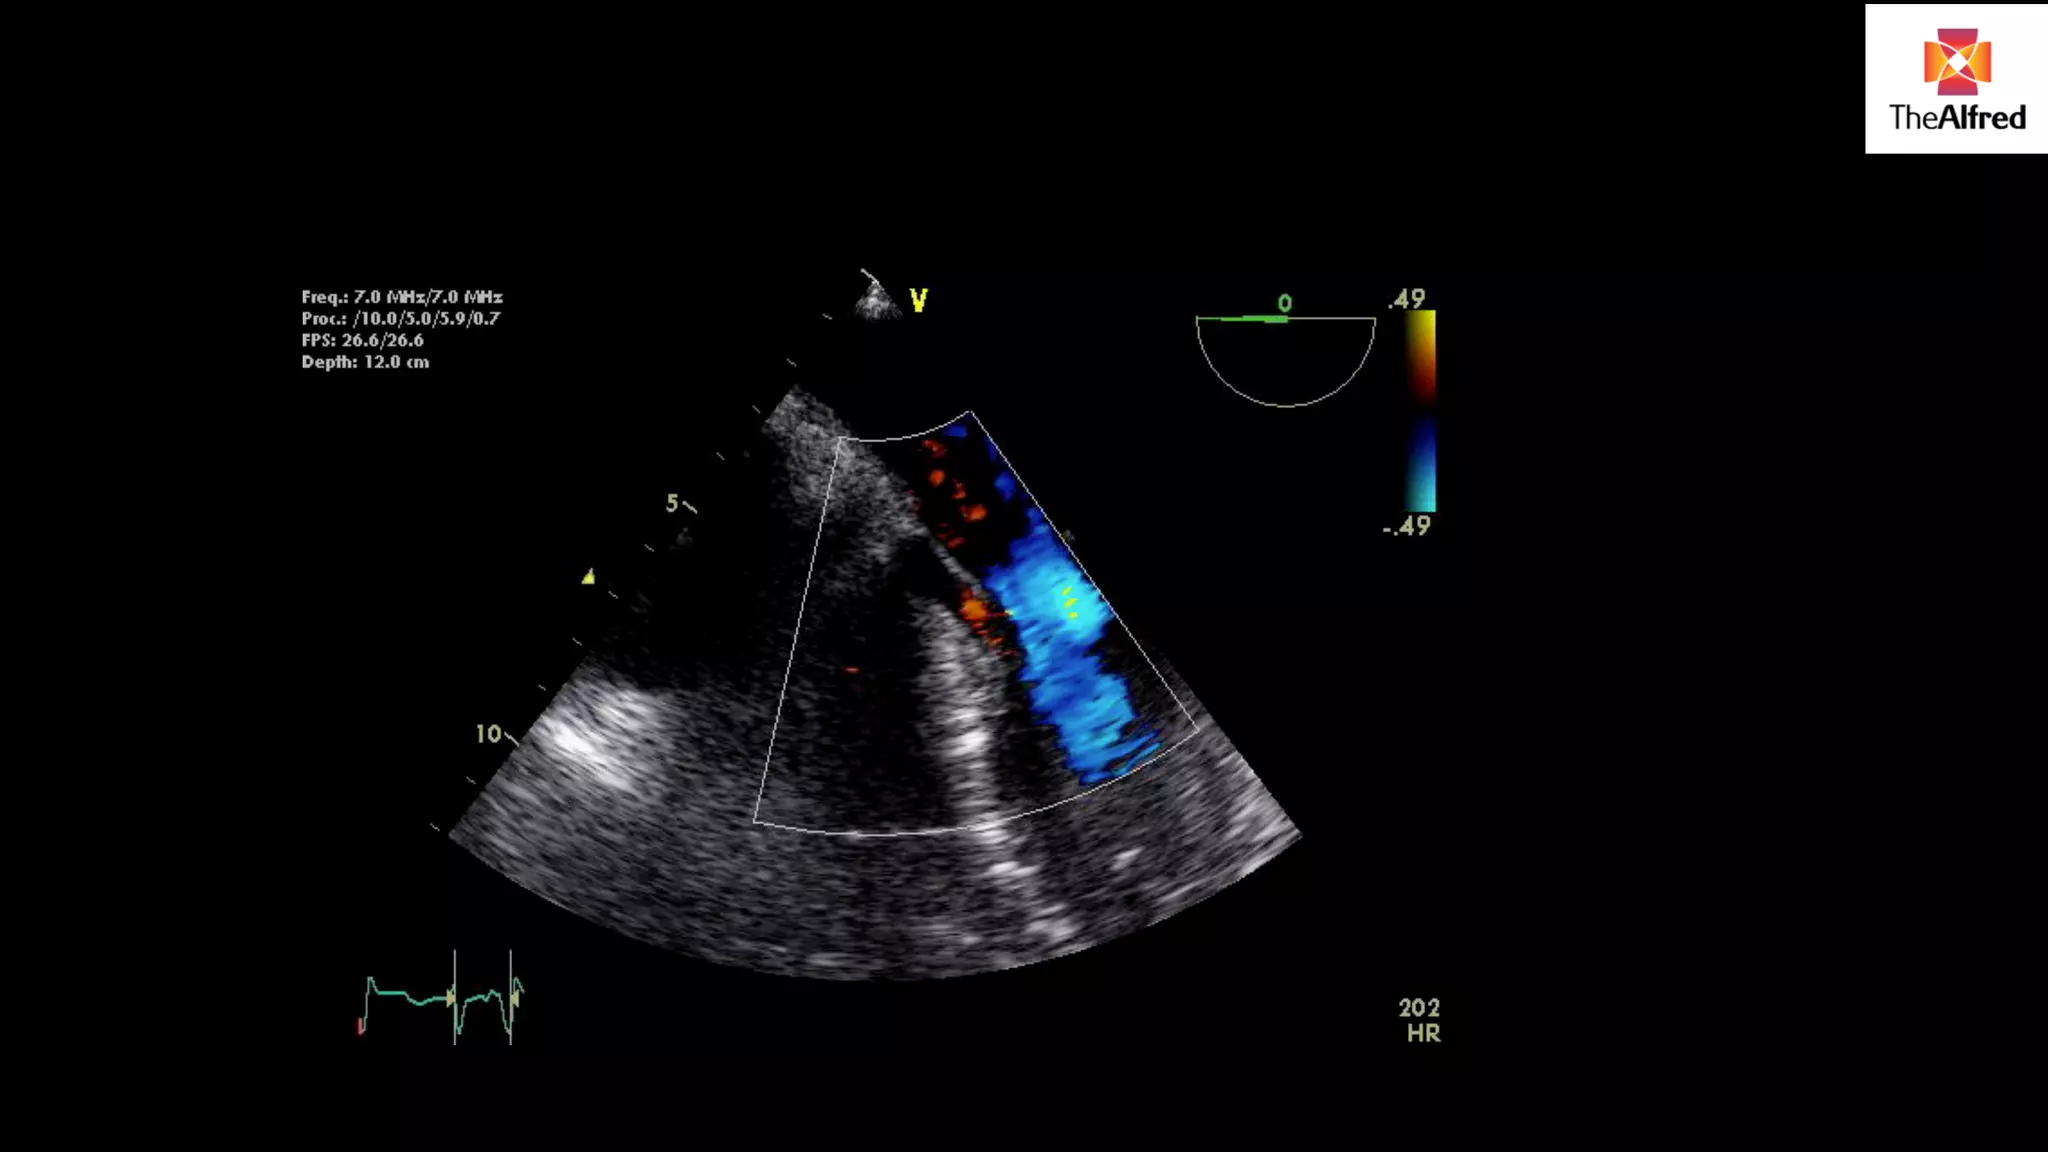

5 chamber

view

3 chamber

USE VIEW WITHTHE BEST DOPPLER LINE UP- DIFFERENT FOR DIFFERENT PATIENTS 5 chamber view 3 chamber view

WHAT ARE THEREQUIREMENTS? Need to evaluate in a number of views to get the best line up with the colour jet